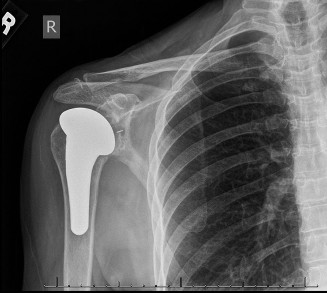

The correct answer is (E). Given that her rotator cuff has atrophied and has fatty infiltration to the point where there are equal parts fat and muscle, this is considered an irreparable rotator cuff tear. Repair should not be attempted because of poor outcomes following repair (see last two paragraphs of this discussion below). A reverse total shoulder arthroplasty is an alternative to repair that should be used in cases of massive, irreparable rotator cuff tears. It is a semi-constrained prosthesis that restores function in patients with massive rotator cuff tears by constraining a concave humeral cap inferior to a semispherical glenoid component (glenosphere). This creates an inferior force-couple and a fulcrum that replaces the stabilizing function of the infraspinatus maintaining a center of rotation around which the shoulder can move. This allows the deltoid to abduct and flex the shoulder without causing the humerus to migrate superiorly and about the acromion. In an elderly patient with a massive, irreparable rotator cuff tear (as in this patient), a reverse total shoulder arthroplasty is the procedure of choice.

It should be noted that reverse total shoulder arthroplasty is also the procedure of choice in patients with cuff-tear arthropathy (aka rotator cuff arthropathy). Characteristics of cuff-tear arthropathy include superior migration of the humerus due to a massive rotator cuff tear, glenohumeral joint destruction, subchondral osteoporosis, and humeral head collapse (see Fig. 2–17). A reverse total shoulder

arthroplasty in this case serves the purpose of eliminating pain caused by glenohumeral joint arthritis while restoring functional motion and is the procedure of choice in patients with cuff-tear arthropathy.

Figure 2–17_X-rays of a patient showing evidence of cuff tear arthropathy. The humerus is migrated superiorly, the glenohumeral joint is destroyed, there is subchondral osteoporosis, and the humeral head is collapsed. (From Ecklund KJ, Lee TQ, Tibone J, Gupta R. Rotator cuff tear arthropathy. _J Am Acad Orthop Surg. 2007;15(6):340–349.)